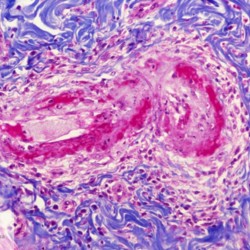

Etiquetes: N-90/90 de 2 Pàgina següent 9 total Canine Specie: Canine Organ: Stomach Lesion: Vasculitis Lesion modifier: - Disease: Leishmaniasis Files/Expedient: N-90/90 Not viewed Canine Specie: Canine Organ: Stomach Lesion: Vasculitis Lesion modifier: - Disease: Leishmaniasis Files/Expedient: N-90/90 Not viewed Canine Specie: Canine Organ: Intestine Lesion: Vasculitis Lesion modifier: - Disease: Leishmaniasis Files/Expedient: N-90/90 Not viewed Canine Specie: Canine Organ: Urinay bladder Lesion: Vasculitis Lesion modifier: - Disease: Leishmaniasis Files/Expedient: N-90/90 Not viewed Canine Specie: Canine Organ: Heart Lesion: Vasculitis Lesion modifier: - Disease: Leishmaniasis Files/Expedient: N-90/90 Not viewed de 2 Pàgina següent Títol Select...Avian (Exotic) (110)Avian (Poultry) (76)Bovine (317)Canine (935)Caprine (47)Equine (257)Feline (326)Ferret (19)General (127)Marine mammal (22)Non-human primate (20)Ovine (328)Porcine (379)Rabbit (61)Reptile (38)Rodent (28)Wildlife (91) Format Select...- (60)Abomasum (37)Adrenal gland (10)Blood (7)Blood vessel (50)Body as a whole (19)Bone (57)Bone marrow (21)Brain (93)Cloaca (1)Diaphragm (2)Ear (5)Esophagus (39)Eye (16)Fetus (12)Gallbladder (23)Gizzard (2)Heart (265)Intestine (356)Joint (32)Kidney (443)Larynx (5)Liver (326)Lung (264)Lymph node (91)Mammary gland (10)Mediastinum (1)Muscle (22)Nasal cavity (22)Nerve (7)Omasum (5)Oral cavity (63)Ovary (14)Oviduct (8)Pancreas (7)Parathyroid (5)Penis (10)Peritoneum (65)Pharynx (9)Pituitary gland (6)Placenta (7)Prostate (8)Proventriculus (3)Reticulum (1)Rumen (28)Sinus (7)Skin (181)Spinal cord (15)Spleen (105)Stomach (125)Teeth (1)Testicle (11)Thoracic cavity (31)Thymus (13)Thyroid gland (5)Tongue (32)Tonsils (11)Trachea (11)Urethra (5)Urinay bladder (61)Uterus (27)Vagina (1)Vulva (1)Yolk sac (1) Cobertura Select...- (152)Abomasitis (26)Abscess (27)Acidosis (1)Adenocarcinoma (20)Adenoma (9)Aerosacculitis (6)Agenesis (1)Agnathia (1)Alopecia (7)Amyloidosis (12)Aneurysm (6)Angiectasis (1)Anthracosis (1)Arteritis (11)Arthritis (15)Arthrogryposis (6)Artifact (4)Ascites (13)Atelectasis (8)Atherosclerosis (5)Atresia (1)Atrial septal defect (2)Atrophy (10)Autolysis (7)Bronchitis (6)Bronchopneumonia (26)Cachexia (2)Carcinoma (103)Cardiomyopathy (19)Cellulitis (2)Chemodectoma (4)Cholangiohepatitis (4)Cholangitis (19)Cholecystitis (4)Cholestasis (5)Chondrodysplasia (2)Chondrosarcoma (2)Chronic passive congestion (13)Chylothorax (2)Cirrhosis (6)Coelomitis (3)Coenurus cerebralis (4)Colitis (40)Congestion (17)Conjunctivitis (5)Coronitis (3)Cryptorchidism (3)Cyst (25)Cystitis (24)Dermatitis (69)Diaphragmatic hernia (4)Dilation (28)Discospondylitis (1)Disseminated intravascular coagulation (7)Dyschondroplasia (1)Dysplasia (29)Ectopia cordis (1)Ectopic ureter (1)Edema (55)Emphysema (5)Encephalitis (5)Endocardiosis (14)Endocarditis (26)Endometritis (5)Enteritis (118)Enterolith (6)Epulis (3)Esophagitis (14)Fasciitis (1)Fibrosis (7)Fibrous osteodystrophy (8)Fistula (1)Folliculitis (3)Fracture (2)Gastritis (34)Gingivitis (5)Glioma (8)Glomerulonephritis (21)Glossitis (25)Glycogenosis (1)Gout (8)Granuloma (2)Granulosa cell tumor (4)Hemangioma (9)Hemangiosarcoma (46)Hematoma (8)Hemoglobinuria (2)Hemopericardium (12)Hemoperitoneum (2)Hemorrhage (100)Hemosiderosis (7)Hemothorax (2)Hepatitis (78)Hernia (11)Histiocytosis (3)Hydatid cyst (11)Hydrocephalus (9)Hydrometra (1)Hydronephrosis (22)Hydropericardium (6)Hydrothorax (3)Hydroureter (5)Hyperkeratosis (8)Hyperostosis (4)Hyperplasia (37)Hypertrophy (9)Hypopigmentation (1)Hypoplasia (7)Hypopyon (1)Impaction (6)Infarction (63)Insulinoma (6)Intussusception (5)Jaundice (17)Laminitis (2)Laryngitis (2)Leiomyoma (5)Leukemia (13)Lipidosis (36)Lipoma (7)Lymphadenitis (45)Lymphadenopathy (7)Lymphangiectasia (6)Lymphangitis (5)Lymphoma (221)Malacia (11)Malignant melanoma (15)Mast cell tumor (11)Mastitis (8)Megaesophagus (2)Melanosis (3)Melena (4)Meningioma (6)Meningitis (6)Meningocele (2)Meningoencephalitis (5)Mesothelioma (5)Methemoglobinemia (2)Mineralization (10)Mucocele (5)Mucometra (1)Multilobular bone tumor (1)Mummification (3)Myelofibrosis (1)Myocarditis (4)Myositis (5)Necrosis (81)Nephritis (113)Nephroblastoma (6)Nephrosclerosis (1)Nephrosis (14)Neuritis (1)Obstruction (13)Omasitis (4)Omphalitis (1)Omphalophlebitis (7)Orchitis (4)Osteoarthrosis (5)Osteomyelitis (9)Otitis (2)Palatoschisis (3)Pancreatitis (3)Panniculitis (3)Papilloma (7)Parakeratosis (14)Patent ductus arteriosus (6)Peliosis hepatis (1)Perforation (17)Pericarditis (35)Peritonitis (39)Persistent right aortic arch (1)Pharyngitis (2)Pheochromocytoma (2)Phlebitis (2)Placentitis (6)Pleuritis (21)Pleuropneumonia (24)Pneumonia (109)Pneumothorax (3)Polycystosis (14)Polyp (5)Polyserositis (6)Posthitis (1)Proctitis (4)Prolapse (3)Prostatitis (3)Proventriculitis (1)Pyelonephritis (24)Pyometra (6)Pyothorax (4)Rhinitis (11)Rumenitis (6)Rupture (24)Salpingitis (3)Sarcoma (57)Sclerosis (1)Scoliosis (2)Seminoma (2)Sequestrum (2)Serous atrophy (14)Sinusitis (7)Splenitis (14)Splenomegaly (9)Spondylitis (6)Spondylosis (1)Stenosis (9)Stomatitis (32)Tenosynovitis (2)Teratoma (3)Thricobezoar (2)Thrombosis (16)Tonsilitis (4)Torsion (13)Tracheitis (4)Tympany (7)Typhlitis (8)Typhlocolitis (4)Ulcer (43)Urethritis (1)Urolithiasis (36)Uroperitoneum (1)Uveitis (1)Vasculitis (15)Ventricular septal defect (3)Volvulus (11) Matèria Select... - (14)- (1653)- (152)Abomasitis - Catarrhal (2)Abomasitis - Catarrhal-hemorrhagic (1)Abomasitis - Chronic (1)Abomasitis - Fibrinous-necrotizing (2)Abomasitis - Hyperplasic (5)Abomasitis - Hyperplasic - Chronic (1)Abomasitis - Necrotic (1)Abomasitis - Necrotizing (2)Abomasitis - Ulcerative (5)Adenocarcinoma (9)Aerosacculitis - Granulomatous (1)Amyloidosis - Chronic (1)Arteritis - Necrotic (2)Arteritis - Necrotizing (1)Arthritis - Chronic (4)Arthritis - Fibrinous-purulent (3)Arthritis - Serous (4)Arthritis - Subacute (1)Ascites - Serous (1)Atrophy - Serous (1)Bronchitis - Catarrhal (3)Bronchitis - Suppurative (1)Bronchopneumonia - Catarrhal-purulent (17)Bronchopneumonia - Fibrinous (1)Bronchopneumonia - Granulomatous (1)Bronchopneumonia - Purulent (1)Bronchopneumonia - Suppurative (5)Carcinoma - Adenocarcinoma (33)Carcinoma - Adenocarcinoma - Hepatocellular (2)Carcinoma - Adenocarcinoma - Mucinous (1)Carcinoma - Basosquamous (1)Carcinoma - Cholangiocellular (3)Carcinoma - Hepatocellular (4)Carcinoma - Metastatic (3)Carcinoma - Squamous cell carcinoma (13)Carcinoma - Transitional cell (2)Cardiomyopathy - Dilated (13)Cardiomyopathy - Hypertrophic (6)Cellulitis - Necrotizing (1)Cholangitis - Chronic (8)Cholangitis - Hyperplasic (3)Cholecystitis - Fibrinous-necrotizing (1)Coelomitis - Fibrinous (1)Coelomitis - Granulomatous (1)Colitis - Catarrhal (3)Colitis - Catarrhal-hemorrhagic (1)Colitis - Fibrinous (1)Colitis - Fibrinous-necrotizing (1)Colitis - Fibrinous-necrotizing (Diphtheritic) (6)Colitis - Granulomatous (2)Colitis - Hemorrhagic (4)Colitis - Hemorrhagic-necrotizing (3)Colitis - Necrotizing (2)Colitis - Ulcerative (6)Congestion - Chronic (2)Conjunctivitis - Hyperplasic (1)Conjunctivitis - Purulent (3)Coronitis - Ulcerative (1)Cystitis - Chronic (3)Cystitis - Fibrinous (1)Cystitis - Fibrinous-necrotizing (1)Cystitis - Follicular (1)Cystitis - Hemorrhagic (6)Cystitis - Hemorrhagic-ulcerative (1)Cystitis - Necrotizing (9)Cystitis - Perforated (1)Dermatitis - Granulomatous (14)Dermatitis - Hyperkeratotic (10)Dermatitis - Hyperplasic (proliferative) (1)Dermatitis - Hyperplastic (10)Dermatitis - Necrotizing (4)Dermatitis - Pustular (4)Dermatitis - Ulcerative (2)Dilation - Chronic (1)Discospondylitis - Necrotizing (1)Dysplasia - Follicular (5)Edema - Interstitial (6)Emphysema - Interstitial (1)Encephalitis - Granulomatous (1)Encephalitis - Nonsuppurative (1)Endocardiosis - Mitral (7)Endocardiosis - Mitral - Chronic (5)Endocarditis - Valvular (6)Endocarditis - Valvular - Mitral (7)Endocarditis - Valvular - Pulmonic (1)Endocarditis - Valvular - Subacute (1)Endocarditis - Valvular - Subaortic (5)Endocarditis - Valvular - Tricuspid (4)Endometritis - Purulent (3)Endometritis - Purulent-hemorrhagic (2)Enteritis - Catarrhal (23)Enteritis - Catarrhal - Acute (1)Enteritis - Catarrhal-hemorrhagic (5)Enteritis - Catarrhal-hemorrhagic - Acute (2)Enteritis - Fibrinous (16)Enteritis - Fibrinous - Acute (3)Enteritis - Fibrinous-necrotizing (7)Enteritis - Granulomatous (14)Enteritis - Granulomatous - Chronic (1)Enteritis - Granulomatous - Multifocal (1)Enteritis - Hemorrhagic (17)Enteritis - Hemorrhagic - Acute (1)Enteritis - Hemorrhagic-necrotizing (1)Enteritis - Hyperplasic (proliferative) (4)Enteritis - Necrotizing (4)Enteritis - Necrotizing - Acute (1)Enteritis - Necrotizing - Hemorrhagic (1)Enteritis - Necrotizing-ulcerative (2)Enteritis - Ulcerative (1)Enteritis - Ulcerative-hemorrhagic (1)Esophagitis - Erosive-ulcerative (6)Esophagitis - Necrotizing (4)Esophagitis - Ulcerative (1)Esophagitis - Ulcerative-necrotizing (1)Fasciitis - Fibrinous-purulent (1)Folliculitis - Purulent (2)Gastritis - Catarrhal (2)Gastritis - Chronic (1)Gastritis - Follicular (1)Gastritis - Hemorrhagic (2)Gastritis - Hemorrhagic-necrotizing (1)Gastritis - Hypertrophic (2)Gastritis - Inclusion bodies (1)Gastritis - Mineralization (1)Gastritis - Mycotic (1)Gastritis - Necrotizing (2)Gastritis - Ulcerative (6)Gastritis - Uremic (3)Gingivitis - Erosive (2)Gingivitis - Hyperplasic (proliferative) (1)Gingivitis - Necrotizing (1)Glomerulonephritis - Chronic (7)Glomerulonephritis - Membranoproliferative (3)Glomerulonephritis - Membranoproliferative - Chronic (1)Glomerulonephritis - Membranous (3)Glomerulonephritis - Membranous - Chronic (1)Glomerulonephritis - Proliferative (2)Glomerulonephritis - Subacute (1)Glossitis - Erosive (2)Glossitis - Granulomatous (6)Glossitis - Hyperplasic (1)Glossitis - Hyperplasic (proliferative) (2)Glossitis - Hyperplastic (1)Glossitis - Necrotizing (2)Glossitis - Necrotizing - Focal (1)Glossitis - Ulcerative (6)Glossitis - Ulcerative - Multifocal (1)Glossitis - Ulcerative - Subacute (1)Glycogenosis (1)Granuloma - Eosinophilic (1)Hemangiosarcoma - Metastatic (2)Hemorrhage - Acute (1)Hemorrhage - Subcapsular (3)Hepatitis - Abscess (9)Hepatitis - Acute (3)Hepatitis - Chronic (4)Hepatitis - Chronic interstitial (6)Hepatitis - Granulomatous (7)Hepatitis - Interstitial - Multifocal (1)Hepatitis - Interstitial - Subacute (1)Hepatitis - Necrotizing (17)Hepatitis - Necrotizing - Acute (2)Hepatitis - Necrotizing - Hemorrhagic (1)Hepatitis - Necrotizing - Subacute (1)Hepatitis - Pyogranulomatous (7)Hepatitis - Subacute (4)Hydronephrosis - Chronic (1)Hydropericardium - Chronic (1)Hyperplasia - Erythroid (1)Hyperplasia - Lymphoid (3)Hyperplasia - Myeloid (1)Hyperplasia - Nodular (8)Hypertrophy - Concentric (2)Hypertrophy - Eccentric (3)Infarction - Acute (17)Infarction - Acute - Multifocal (2)Infarction - Chronic (5)Infarction - Chronic - Multifocal (1)Infarction - Subacute (18)Infarction - Subacute - Focal (2)Laminitis - Chronic (2)Laryngitis - Necrotic (1)Laryngitis - Necrotizing (1)Leukemia - Lymphoid leukemia (2)Leukemia - Non-lymphoid leukemia (6)Lipidosis - Multifocal (1)Lipidosis - Panlobular (1)Lipidosis - Panlobular - Generalized (2)Lymphadenitis - Granulomatous (24)Lymphadenitis - Granulomatous - Chronic (3)Lymphadenitis - Hemorrhagic (1)Lymphadenitis - Necrotizing (5)Lymphadenitis - Necrotizing (caseous) (11)Lymphangitis - Granulomatous (1)Lymphangitis - Purulent (1)Lymphangitis - Ulcerative (1)Lymphoma - Alimentary lymphoma (7)Lymphoma - Cutaneous lymphoma (6)Lymphoma - Lymphosarcoma (2)Lymphoma - Mediastinal lymphoma (1)Lymphoma - Multicentric lymphoma (29)Malignant melanoma - Malignant (1)Malignant melanoma - Metastatic (1)Mast cell tumor - Metastatic (1)Mastitis - Fibrinous-purulent (2)Mastitis - Necrotic (1)Mastitis - Purulent (3)Mastitis - Suppurative (1)Meningitis - Fibrinous-purulent (2)Meningitis - Purulent (4)Meningoencephalitis - Necrotizing (3)Meningoencephalitis - Nonsuppurative (2)Mineralization - Metastatic (4)Myocarditis - Fibrous - Chronic (1)Myocarditis - Granulomatous (1)Myositis - Purulent (2)Necrosis - Acute (1)Necrosis - Cortical (5)Necrosis - Follicular (1)Necrosis - Papillary (8)Necrosis - Papillary - Acute (3)Necrosis - Subacute (3)Necrosis - Tubular (6)Nephritis - Embolic (2)Nephritis - Embolic suppurative (7)Nephritis - Granulomatous (27)Nephritis - Granulomatous - Chronic (1)Nephritis - Granulomatous - Multifocal (1)Nephritis - Interstitial (6)Nephritis - Interstitial - Acute (4)Nephritis - Interstitial - Chronic (41)Nephritis - Interstitial - Subacute (12)Nephritis - Purulent (7)Nephritis - Purulent - Acute (2)Nephritis - Purulent - Multifocal (3)Nephrosis - Cholemic (3)Nephrosis - Hemoglobinuric (10)Omasitis - Fibrinous-necrotizing (1)Omasitis - Hyperkeratotic (1)Omasitis - Necrotizing (2)Omphalophlebitis - Fibrinous-purulent (2)Omphalophlebitis - Purulent (3)Orchitis - Necrotizing (1)Osteomyelitis - Necrotizing (7)Osteomyelitis - Purulent (2)Otitis - Necrotizing (1)Otitis - Proliferative (1)Pancreatitis - Acute (1)Pancreatitis - Chronic (1)Pancreatitis - Granulomatous (1)Panniculitis - Fibrinous-purulent (1)Panniculitis - Necrotic (1)Panniculitis - Parasitic (1)Perforation - Acute (2)Pericarditis - Fibrinous (19)Pericarditis - Fibrinous - Subacute (1)Pericarditis - Fibrinous-necrotizing (1)Pericarditis - Fibrinous-purulent (3)Pericarditis - Fibrous (1)Pericarditis - Fibrous - Chronic (1)Pericarditis - Gangrenous (6)Pericarditis - Granulomatous (1)Pericarditis - Granulomatous - Chronic (2)Peritonitis - Acute (1)Peritonitis - Fibrinous (11)Peritonitis - Fibrinous - Subacute (1)Peritonitis - Fibrinous-purulent (5)Peritonitis - Fibrous (3)Peritonitis - Granulomatous (6)Peritonitis - Purulent (1)Peritonitis - Purulent-hemorrhagic (1)Peritonitis - Pyogranulomatous (3)Pharyngitis - Fibrinous-necrotizing (1)Pharyngitis - Ulcerative (1)Pheochromocytoma - Metastatic (1)Phlebitis - Purulent (1)Placentitis - Fibrinous-necrotizing (1)Placentitis - Necrotic (1)Placentitis - Necrotizing (1)Pleuritis - Chronic (1)Pleuritis - Fibrinous (3)Pleuritis - Fibrinous-purulent (2)Pleuritis - Fibrous (2)Pleuritis - Granulomatous (3)Pleuritis - Hyperplastic (2)Pleuritis - Purulent (2)Pleuritis - Pyogranulomatous (1)Pleuropneumonia - Fibrinous (13)Pleuropneumonia - Fibrinous-necrotizing (5)Pleuropneumonia - Granulomatous (2)Pleuropneumonia - Hemorrhagic-necrotizing (4)Pneumonia - Aspiration (11)Pneumonia - Bronchointerstitial (4)Pneumonia - Bronchointerstitial - Subacute (1)Pneumonia - Embolic (5)Pneumonia - Granulomatous (37)Pneumonia - Granulomatous - Multifocal (4)Pneumonia - Hemorrhagic-necrotizing (2)Pneumonia - Interstitial (7)Pneumonia - Interstitial - Acute (8)Pneumonia - Interstitial - Chronic (6)Pneumonia - Interstitial - Subacute (15)Pneumonia - Necrotizing (2)Pneumonia - Pyogranulomatous (2)Pneumonia - Verminous (5)Polyserositis - Fibrinous (6)Polyserositis - Fibrous (1)Proctitis - Fibrinous-necrotizing (1)Proctitis - Parasitic (2)Prostatitis - Purulent (1)Pyelonephritis - Acute (2)Pyelonephritis - Chronic (3)Rhinitis - Catarrhal (2)Rhinitis - Fibrinous (1)Rhinitis - Granulomatous (4)Rhinitis - Purulent (3)Rumenitis - Acute (1)Rumenitis - Erosive (1)Rumenitis - Necrotizing (1)Rupture - Acute (3)Sarcoma - Fibrosarcoma (12)Sarcoma - Hemangiosarcoma (11)Sarcoma - Histiocytic (7)Sarcoma - Metastatic (1)Sarcoma - Multilobular tumor of bone (1)Sequestrum - Chronic (2)Sinusitis - Suppurative (1)Splenitis - Granulomatous (8)Splenitis - Granulomatous - Chronic (1)Splenitis - Necrotizing (3)Splenitis - Necrotizing (caseous) (2)Spondylitis - Necrotizing (2)Stenosis - Intestinal (1)Stenosis - Valvular - Subaortic (4)Stomatitis - Erosive (12)Stomatitis - Erosive-ulcerative (3)Stomatitis - Fibrinous-necrotizing (1)Stomatitis - Fibrinous-necrotizing (Diphtheritic) (1)Stomatitis - Granulomatous (1)Stomatitis - Hyperplasic (1)Stomatitis - Hyperplasic (proliferative) (1)Stomatitis - Necrotizing (2)Stomatitis - Ulcerative (5)Stomatitis - Ulcerative - Multifocal (1)Stomatitis - Ulcerative-necrotizing (1)Tonsilitis - Necrotizing (4)Torsion - Acute passive hyperemia (5)Tracheitis - Catarrhal (3)Tracheitis - Fibrinous (1)Tracheitis - Granulomatous (1)Typhlitis - Catarrhal (1)Typhlitis - Fibrinous-necrotizing (2)Typhlitis - Hemorrhagic (2)Typhlitis - Ulcerative-hemorrhagic (1)Typhlocolitis - Fibrinous-necrotizing (2)Typhlocolitis - Proliferative (1)Ulcer - Chronic (6)Ulcer - Multifocal (2)Ulcer - Mycotic (1)Ulcer - Perforated (6)Urethritis - Hemorrhagic (1)Urolithiasis - Chronic (2)Uveitis - Granulomatous (1)Vasculitis - Granulomatous (1)Vasculitis - Necrotizing (1) Editor Select...- (1970)Acidosis (2)Actinobacillosis (Pleuropneumonia) (11)Aelurostrongylosis (2)African horse sickness (13)African swine fever (14)Alopecia X (1)Anaplasmosis (4)Anthrax (2)Aortic thromboembolism (feline) (7)Ascariasis (15)Aspergillosis (18)Atopic dermatitis (1)Atrophic rhinitis (3)Babesiosis (6)Blackhead (1)Bluetongue (11)Border disease (2)Bovine viral diarrhea (21)Brucellosis (2)Candidiasis (5)Canine distemper (14)Caprine arthritis-encephalitis (2)Capture myopathy (1)Cardiac insufficiency (17)Caseous lymphadenitis (7)Chlamydiosis (2)Classical swine fever (19)Clostridiosis (19)Coccidiosis (9)Coenurosis (4)Colibacillosis (21)Contagious ecthyma (7)Copper toxicosis (11)Cowdriosis (Heartwater) (3)Cryptococcosis (3)Cryptosporidiosis (2)Cysticercosis (23)Demodicosis (1)Diabetes (1)Dicrocoeliosis (5)Dictyocaulosis (4)Dirofilariasis (7)Discoid lupus erythematosus (3)Echinococcosis (17)Edema disease (7)Egg drop syndrome (1)Encephalitozoonosis (5)Enterotoxemia (1)Enzootic bovine leukosis (46)Epitheliogenesis imperfecta (3)Equine rhinopneumonitis (2)Equine verminous arteritis (strongylosis) (7)Erysipelas (5)Exudative epidermitis (7)Fasciolasis (11)Feline eosinophilic dermatoses (1)Feline hepatic lipidosis (8)Feline histiocytosis (4)Feline infectious peritonitis (38)Feline leukemia (4)Feline lower urinary tract disease (3)Feline panleukopenia (16)Feline viral rhinotracheitis (1)Flea allergy dermatitis (1)Foot and mouth disease (2)Gasterophilosis (4)Glasser's disease (15)Gousiekte (4)Gout (6)Haemonchosis (9)Hemolytic anemia (4)Hemorrhagic diathesis (1)Hepatic insufficiency (11)Hepatosis dietetica (7)Herpesvirosis (6)Hyperadrenocorticism (7)Hyperparathyroidism (10)Hypertrophic osteopathy (6)Hypervitaminosis D (1)Hypodermosis (1)Inclusion body hepatitis (4)Infectious bovine rhinotracheitis (5)Infectious bronchitis (5)Infectious canine hepatitis (13)Influenza (4)Juvenile nephropathy (8)Lamb dysentery (4)Leishmaniasis (28)Leptospirosis (1)Leukosis (5)Listeriosis (4)Lumpy skin disease (3)Maedi-visna (4)Malignant catarrhal fever (12)Mange (6)Mannheimiosis (5)Marek's disease (7)Metabolic bone disease (2)Mucoid enteropathy (5)Mulberry heart disease (5)Myasis (1)Mycobacteriosis (22)Mycosis fungoides (6)Myxomatosis (3)Necrobacillosis (5)Neonatal isoerythrolysis (6)Nocardiosis (4)Oestrosis (2)Onchocerciasis (1)Osteochondrosis (1)Ostertagiosis (6)Ovine pulmonary adenocarcinoma (5)Oxyuriasis (1)Pacheco's disease (4)Papillomatosis (6)Paratuberculosis (18)Parvovirosis (17)Pasteurellosis (11)Pemphigus foliaceus (1)Periodontal disease (1)Polioencephalomalacia of ruminants (4)Polyarteritis nodosa (3)Polycystic kidney disease (13)Porcine circovirosis (11)Porcine dermatitis and nephropathy syndrome (9)Porcine proliferative enteropathy (4)Porcine reproductive and respiratory syndrome (6)Porcine stress syndrome (1)Pox (13)Pregnancy toxemia (3)Proventricular dilatation disease (2)Pseudotuberculosis (yersiniosis) (2)Psittacine beak and feather disease (PBFD) (5)Pyoderma (4)Q fever (4)Rabbit hemorrhagic disease (2)Renal insufficiency (12)Reticuloendotheliosis (2)Rhodococcosis (1)Rickets (1)Rinderpest (2)Salmonellosis (34)Sarcosporidiosis (2)Schmallenberg (7)Septicemia (23)Spirocercosis (11)Streptococcosis (5)Strongylosis (1)Swine dysentery (5)Systemic coronavirosis (5)Tetralogy of Fallot (5)Theileriosis (13)Thromboembolism (5)Toxoplasmosis (11)Transmissible viral proventriculitis (1)Traumatic reticuloperitonitis (3)Traumatism (16)Tuberculosis (58)Ulcerative lymphangitis (1)Uremic syndrome (20)Viral arthritis (6)White muscle disease (9)Wobbler syndrome (2)Xanthomatosis (1)Zygomycosis (4) Idioma Select...- (1180)Bacterial (501)Degeneration (106)Fungal (46)Hemodynamic (112)Idiopathic (22)Inflammation (58)Malformation (88)Neoplasia (343)Nutritional (41)Parasitic (243)Physical/Chemical (93)Toxic (44)Viral (304) Ítem destacat Avian (Poultry) Broilers. Livers are swollen, pale, friable with petechial or echymotic hemorrhages. Adenovirus (group I).